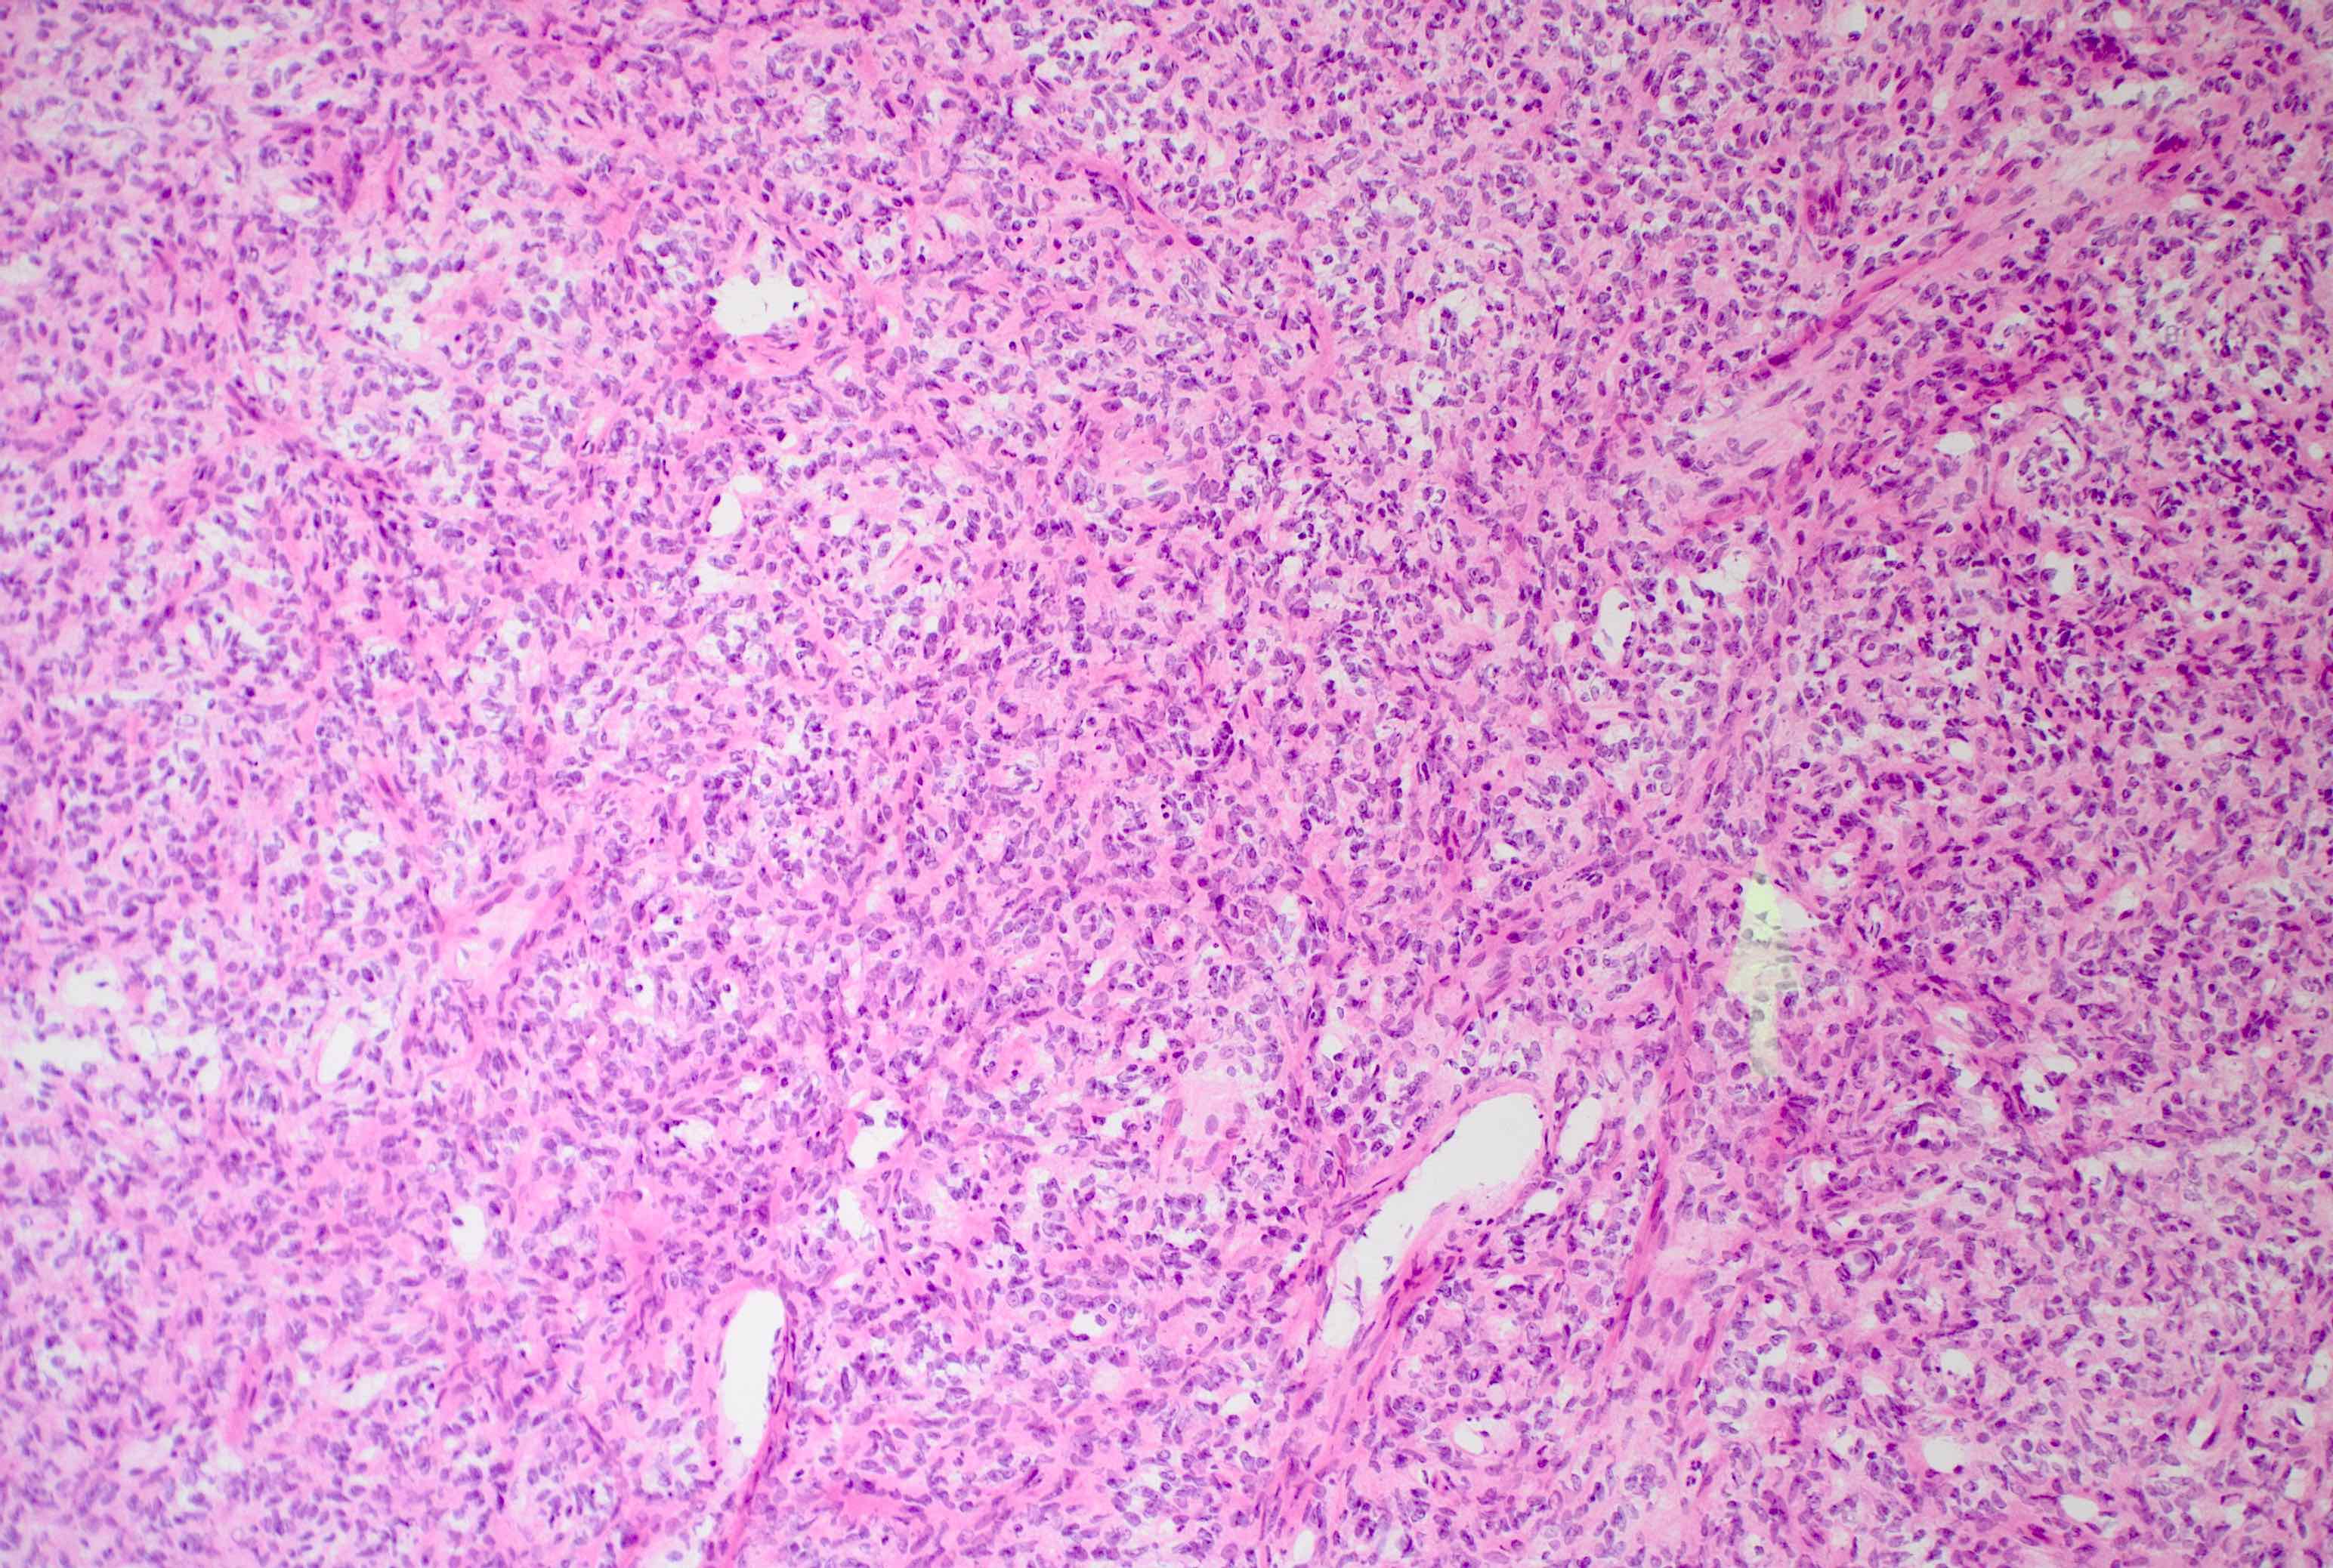

Microscopic (histologic) description

- Essential: patternless pattern of spindle cells, often solid but can also have papillary and other architectures, arranged around branching hyalinized vessels

- Varying amounts of stromal collagen and overall cellularity

- Nuclei are bland, without features seen in mimicking neoplasms

- WHO grading criteria:

- < 5 mitoses/10 high power fields (HPF) = grade 1

- ≥ 5 mitoses/10 HPF = grade 2

- ≥ 5 mitoses/10 HPF with necrosis = grade 3

- Often has staghorn vasculature

Microscopic (histologic) images